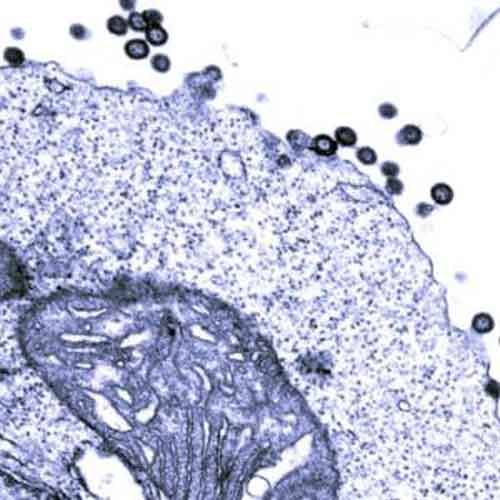

Ricercatori provenienti da Repubblica Ceca e Germania hanno scoperto per la prima volta la dettagliata struttura del guscio che circonda il materiale genetico dei retrovirus, nel momento in cui si formano, una fase fondamentale e potenzialmente vulnerabile del loro ciclo vitale.

I retrovirus sono fatti di un materiale genetico racchiuso in un guscio di proteina, che a sua volta è circondato da una membrana. Per quanto riguarda l’HIV, dopo che un retrovirus entra in una delle cellule del nostro sistema immunitario, il virus si replica, producendo più copie di sé stesso, ognuna delle quali deve essere assemblata da un misto di componenti cellulari e virali in un virus immaturo.

Sia il guscio del virus maturo che quello del virus immaturo sono reticoli a nido d’ape di forma esagonale. Usando un insieme di microscopia elettronica e metodi computerizzati, il team ha potuto studiare quali parti delle proteine si uniscono per costruire il reticolato del guscio immaturo. Queste si sono rivelate essere molto diverse dalle parti che costruiscono il guscio maturo.